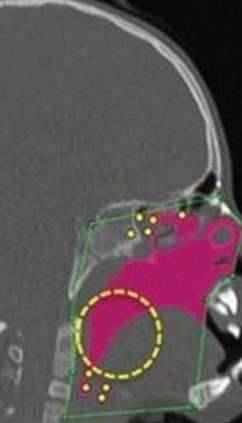

▼哈波医生成功地执行了这项手术,手术后,汉娜的气管从一开始极为狭窄的状况,终于被扩通!